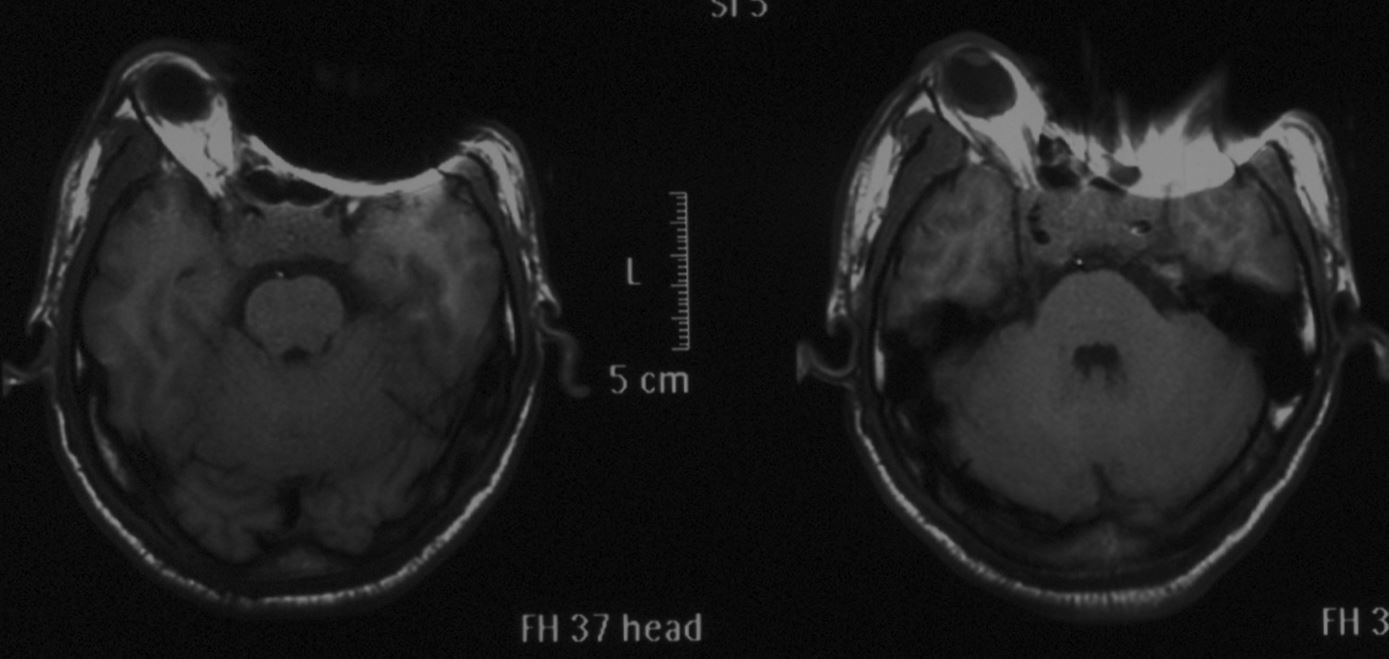

头颅MRI示:鞍区占位性病变,肿瘤大小约2*2.8cm,T1等信号,T2混杂信号,增强后部分强化。肿瘤刚突破鞍底向蝶窦生长,向上突破鞍隔向上生长,视交叉明显受压,左侧较为严重。肿瘤向两侧生长,海绵窦及颈内动脉受侵犯。垂体瘤卒中可能大。